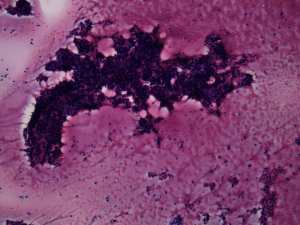

Cytological diagnosis: benign colloid goiter.